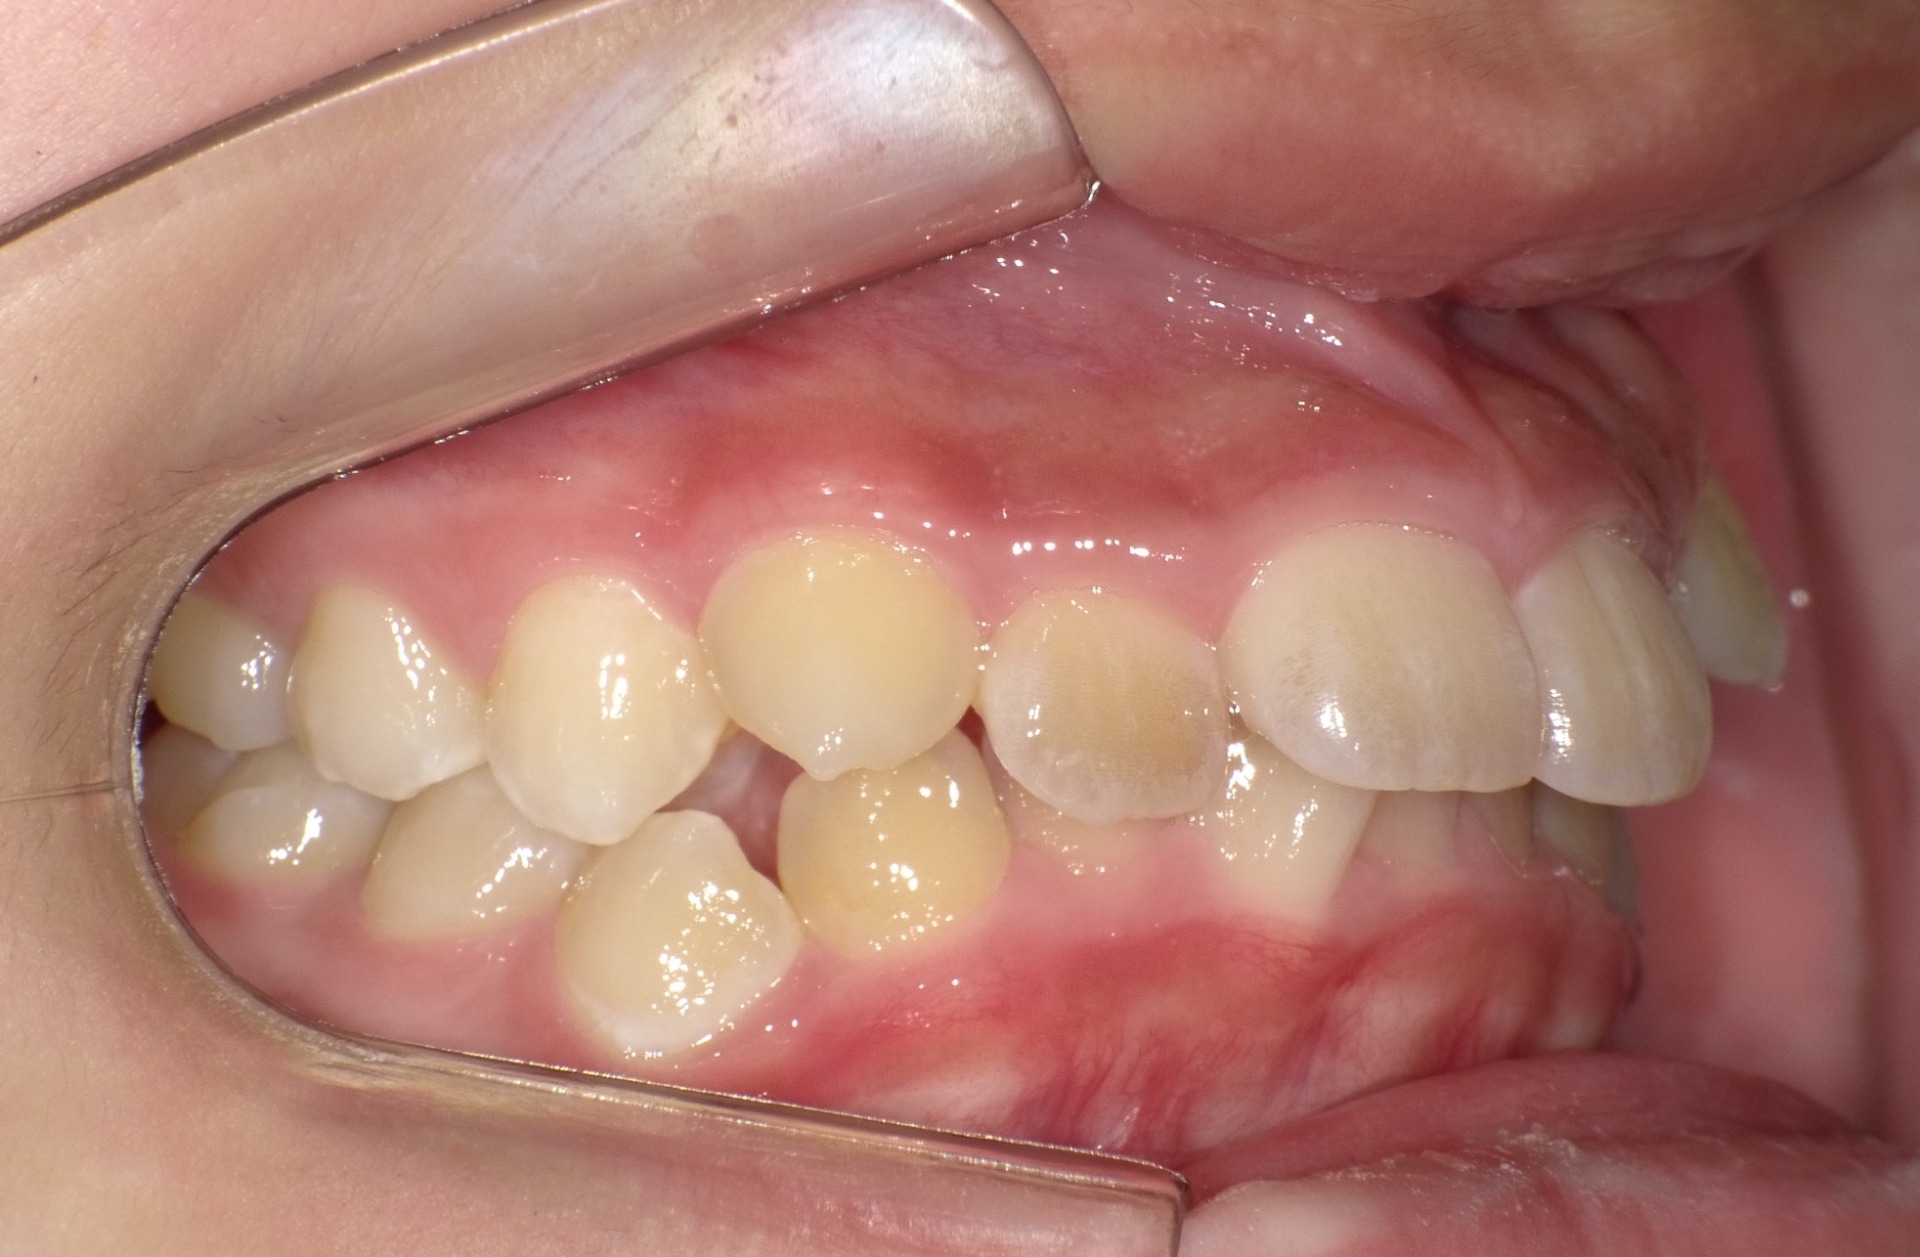

矯正前

| 症状 | 上顎前突 過蓋咬合 |

| 通院時の 年齢 |

8才1ヶ月〜15才10ヶ月 |